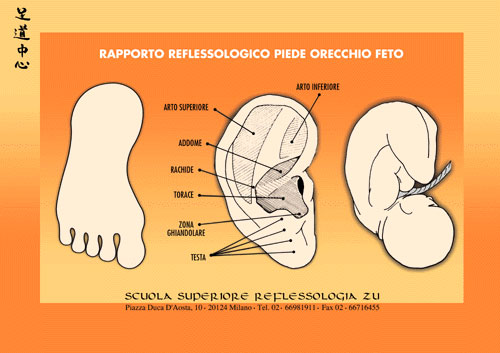

Reflessologia Libro 1 Il Piede tra Micro e Macrocosmo